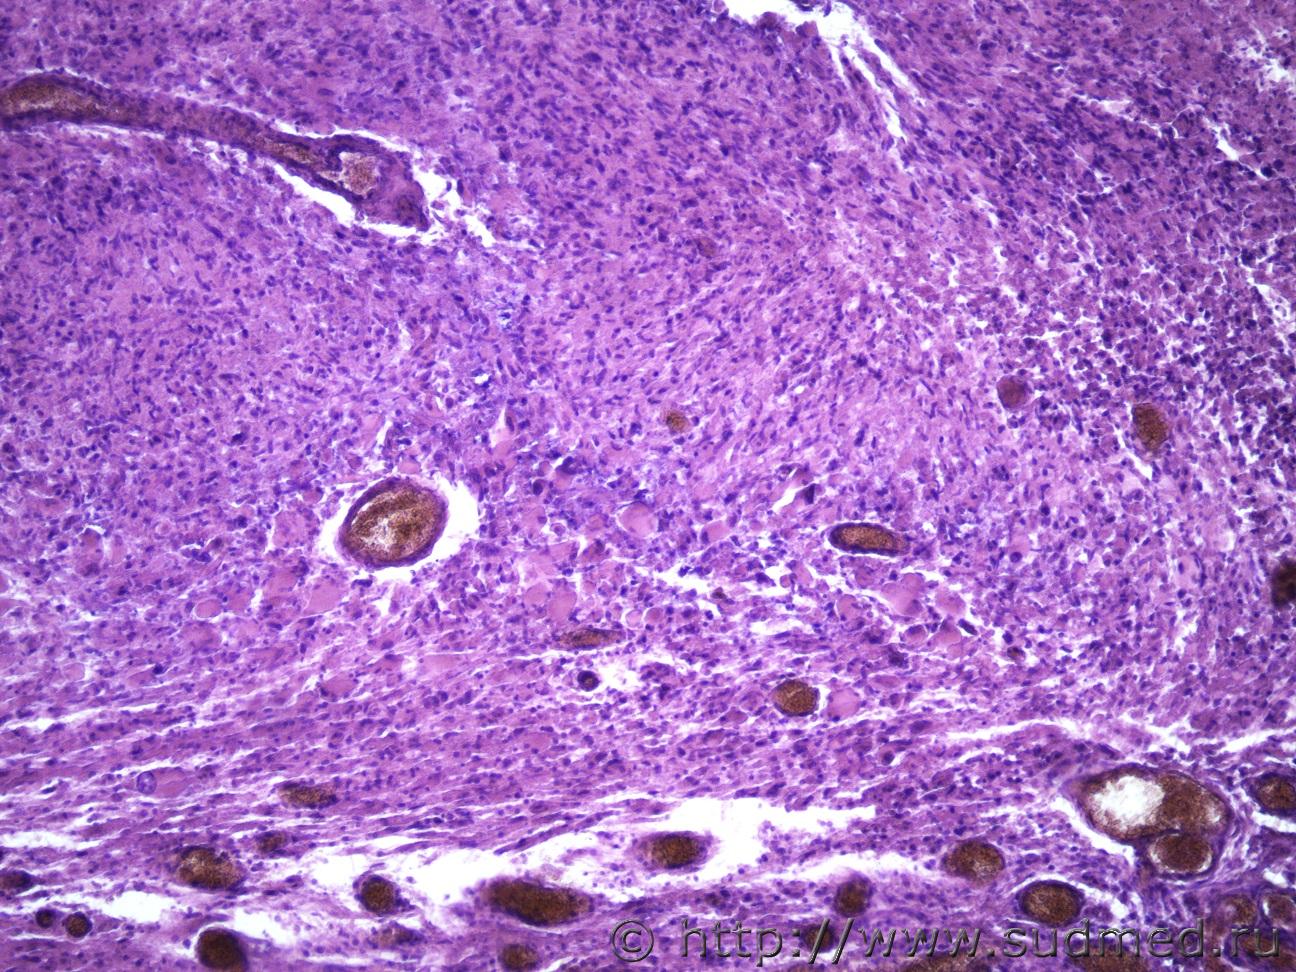

Ув. коллеги, как всегда нужна ваша помощь. Муж 80 лет отходящее от тмо новообразование от беловато-серого до темно-коричневого цвета с вдавлением в вещество головного мозга. Предполагается менингиома. Очень интересуют изменения в самом головном мозге в проекции с давления опухолью. ТМО Судебная медицина - Прикрепленное изображение Судебная медицина - Прикрепленное изображениеСудебная медицина - Прикрепленное изображениеСудебная медицина - Прикрепленное изображениеСудебная медицина - Прикрепленное изображение

Если локализация точно из ММО, то соответствует на рабдоидный тип менигиомы, если нет, то метастатически м.б.

Скорее так.

С80.